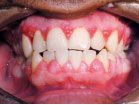

Hormonal changes in pregnancy in the presence of even small pre-existing plaque biofilm deposits and inflammation can result in moderate to severe clinical gingival inflammation and enlargement, often accompanied with an inflammatory granulomatous tissue overgrowth. Certain medications, including dilantin for seizures, cyclosporine to prevent transplant rejection (Fig. 2), or certain calcium channel blockers for treating hypertension and/or cardiac arrhythmias, also can lead to inflammatory and/or fibrotic gingival enlargement of the gingival tissues. Patients on methotrexate therapy often present with ulcerations of the gingival tissue.